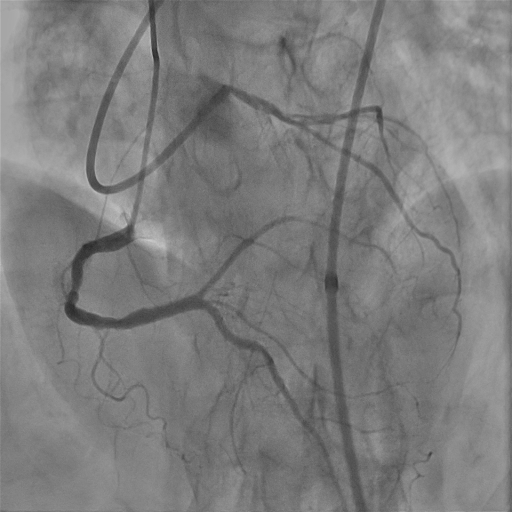

We used 7Fr EBU 3.5 guiding catheter to provide strong support, with diagnostic JR4 as contralateral injection. We started with antegrade wiring, which turned out to be difficult. There seemed to be a little bit of stump in the proximal cap but wire manipulation towards the stump was difficult, owing to the bending angle right at left main trifurcation as well as presence of calcium nodule in ostial stent. We failed proximal cap puncture despite escalating to Conquest Pro 12 loaded in single lumen microcatheter (SLC), which often backed off upon wire probing. Balloon assisted power puncture failed as well. To overcome the acute bending hindering wiring force exertion, we switched to an angulated microcatheter SuperCross120. By this manouvre we were able to advance our wire slightly into very proximal part of LAD stent, but it was deviated from central lumen and we failed to track down SLC. Hence we switched to parallel wire technique with use of a dual lumen microcatheter. The 2nd wire was able to reach the distal part of the stent only despite switching back to SLC and 1.0 balloon dilatation. Our next step was using the 0.9mm laser catheter to perform calcium modification within the ISR segment sequentially with saline, blood and contrast medium. After this manouvre, LAD was finally successfully wired with Fielder XTA, followed by balloon dilatation under IVUS guidance. Balloon expansion in ISR was suboptimal, hence it was treated with shockwave and drug coated balloon.

Laser.avi

Laser1.avi